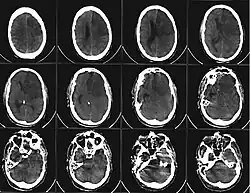

![]() Компьютерная томограмма головного мозга, демонстрирующая инфаркт в правом полушарии головного мозга (зона инфаркта обведена красным.) | |